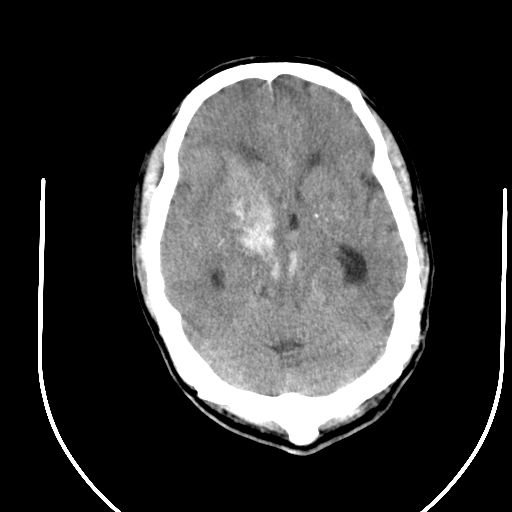

1右侧基底节脑出血伴脑干出血并破入脑室系统脑疝形成2梗阻性脑积水

1)右侧基底节脑出血伴脑干出血并破入脑室系统。2)大脑镰下疝。3)梗阻性脑积水。

1、右侧基底节脑出血伴脑干出血并破入脑室系统。

2、大脑镰下疝。

3、梗阻性脑积水。